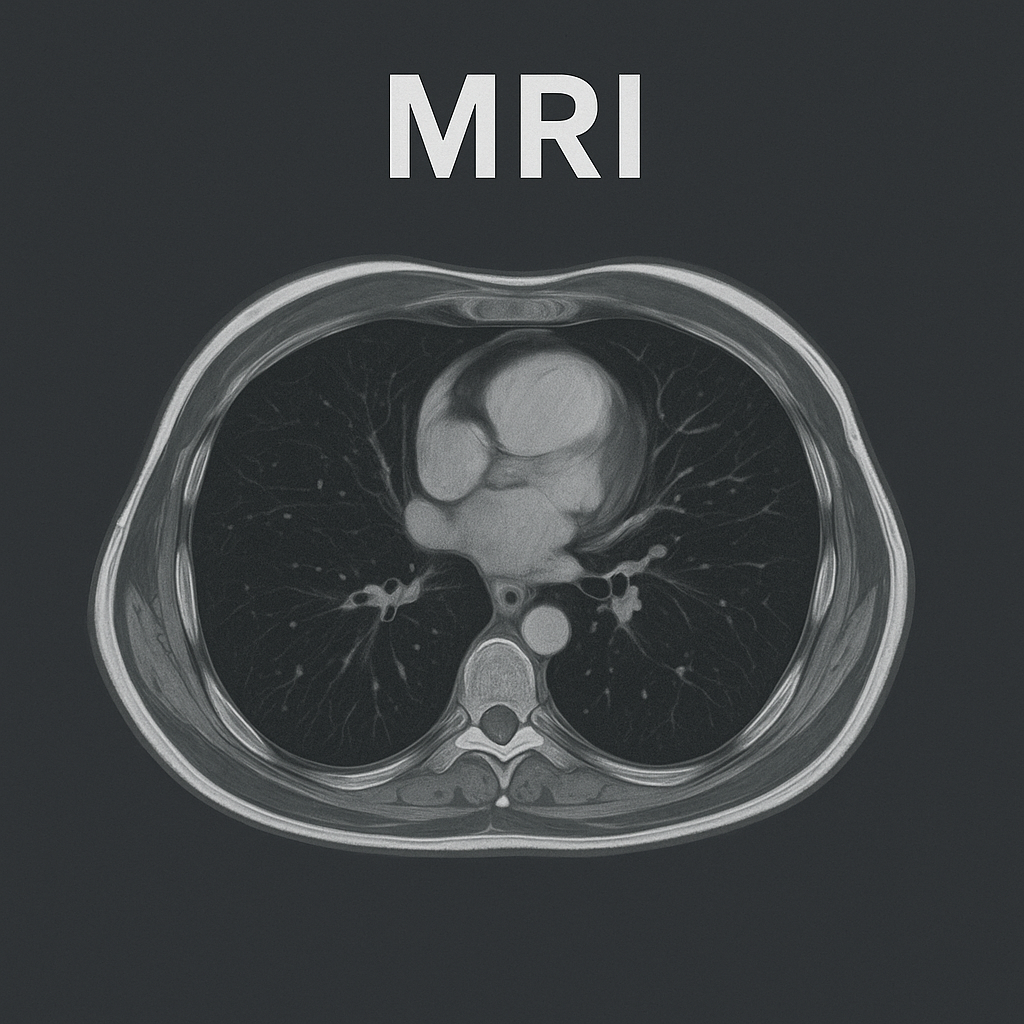

MRI (એમ. આર. આઇ):

- MRI – મેગ્નેટિક રેઝોનન્સ ઇમેજિંગ

- MRI માં પાવરફુલ મેગ્નેટ અને રેડિયો વેવ્સ નો ઉપયોગ કરવામાં આવે છે અને આપેલ એરિયાનો ક્રોસસેક્શન ઈમેજ ક્રિએટ કરવામાં આવે છે.

- MRI એ હાર્ટ, લંગ અને બ્લડ વેસેલ્સની ડિટેલમાં ઇન્ફોર્મેશન પૂરી પાડે છે.

- MRI ની મદદથી પલ્મોનરી નોડયુલ્સ, ફાયબ્રોસિસ, પ્લુરલ ડીઝીસ અને વાસ્કયુલર એબનોર્મલીટીને ડિટેક્ટ કરી શકાય છે.